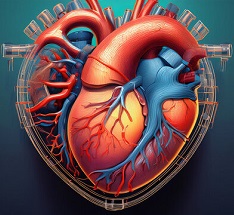

Surgical Procedures

Surgery is commonly required to repair structural or functional health issues and to restore healthy body functionality. Surgery is a crucial interventional procedure that can save lives and vastly enhance the quality of life in cardiology and general health management. Dr Ebrahim Patel, MBBS, DNB (CVTS), is an accomplished surgeon practising in Pune who has offered more than just surgery, but with a patient-first approach.

Speciality in Heart Surgeries

Dr. Patel is a highly skilled cardiac surgeon specialising in complex heart surgeries such as repairing congenital heart defects, valve replacement and valve repair surgeries, and bypasses. His treatment plans aim at precision, safety, and quicker recovery to secure the heart health of elderly and young patients.